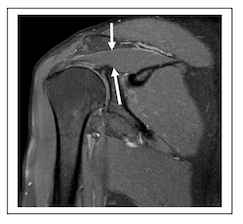

14-48 MR画像を以下に示す.描出されているものはどれか。3つ選べ。

MRI認定 総集 ランダム